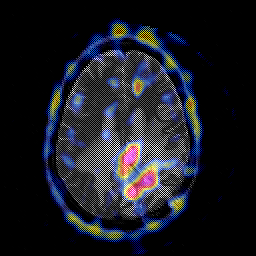

Glioblastoma multiforme overlay -- Slice #35

[Home][Help][Clinical][Tour 1][Tour 2][Tour 3] Slice 35